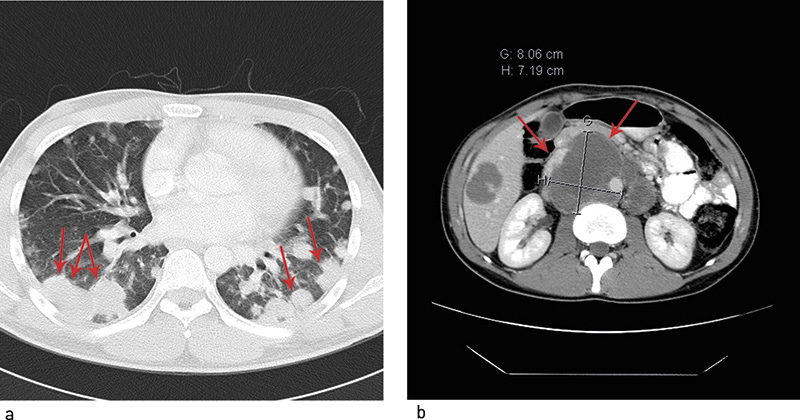

Fem måneder etter oppstart av kjemoterapi ble det utført bilateralt retroperitonealt glandeltoilette. Histologisk undersøkelse av resektatet viste nekrotiske metastaser og en liten rest av modent teratom. På dette tidspunktet hadde han normale tumormarkører, men over 50 resterende lungelesjoner. Han ble vurdert med tanke på torakotomi og reseksjon av restlesjoner. Operasjon var imidlertid utelukket da lesjonene gjennomgående var små (< 2 cm), og i et høyt antall. Ved gjentatte bildekontroller var det tilbakegang av lungeforandringene, som ble oppfattet som sannsynlig ikke-viabelt restvev med lavt opptak ved FDG-PET-undersøkelser (fig 2).